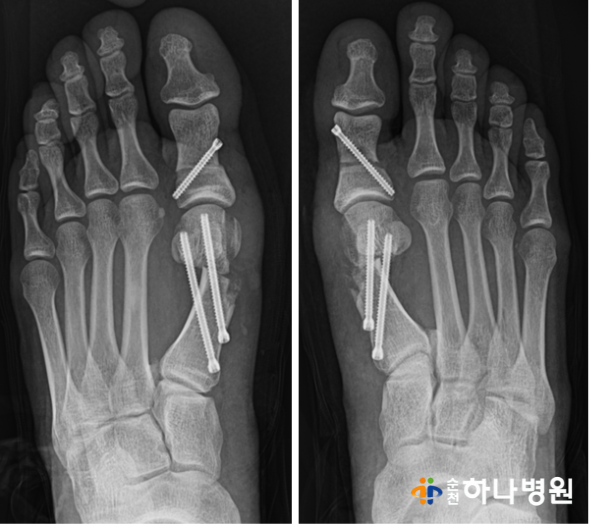

2) 수술직후 : 4세대 미타(MITA)로 교정

수술 직후 x-ray 사진입니다.

수술 전과 비교했을때 확연히

달라진 것을 확인할 수 있습니다!

무지외반증 수술 후 각도 확인 결과

우측 ( 무지외반각도 31' / 제 1-2중족골간각도 16')

→ (무지외반각도 9' / 제1-2중족골간각도 7')

좌측 (무지외반각도 25' / 제1-2 중족골간각도 16')

→ (무지외반각도 9' / 제1-2 중족골간각도 8')

모두 중등도 변형에서 '정상'으로 회복된 모습을

확인할 수 있습니다.

사진에서도 보시다시피

양측 모두 엄지발가락 2번째 발가락을 밀지 않고

평행한 모습을 보실 수 있습니다^^

제1중족골두가 툭 뒤어 나와있던

부분 또한 없어진 모습!